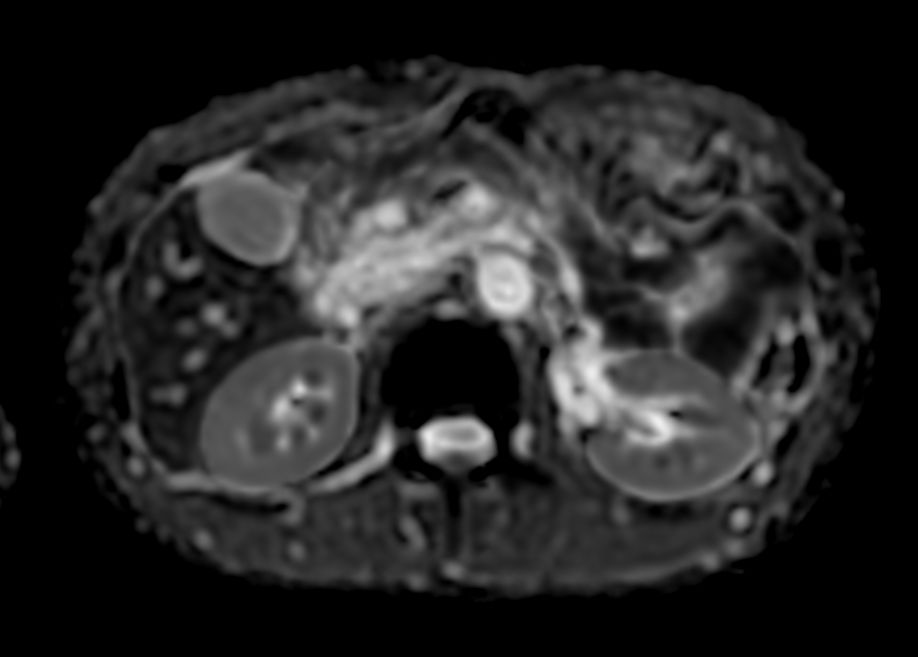

Diffusion - b800

Diffusion - b800 (ADC)